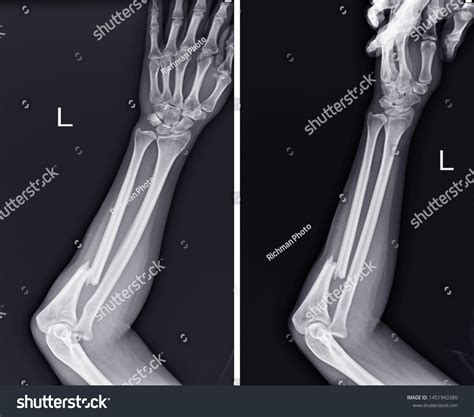

Anteroposterior (AP) View The arm is flat on the table, palm facing up, providing a front-to-back view of the radius and ulna.

Lateral View The arm is turned 90 degrees, showing the side profile of the bones to check for displacement or angling.

To interpret a forearm X-ray, it helps to understand the anatomy involved. The forearm consists of two long bones that work together to allow for flexibility and rotation:

The Radius: Located on the side of the thumb, the radius is the bone that primarily allows the forearm to rotate, enabling you to turn your palm up or down.

The Ulna: Located on the side of the pinky finger, the ulna is larger at the elbow and helps form the hinge joint necessary for bending the arm.

• Dislocations: Ensuring the bones of the elbow and wrist remain properly seated in their joints.